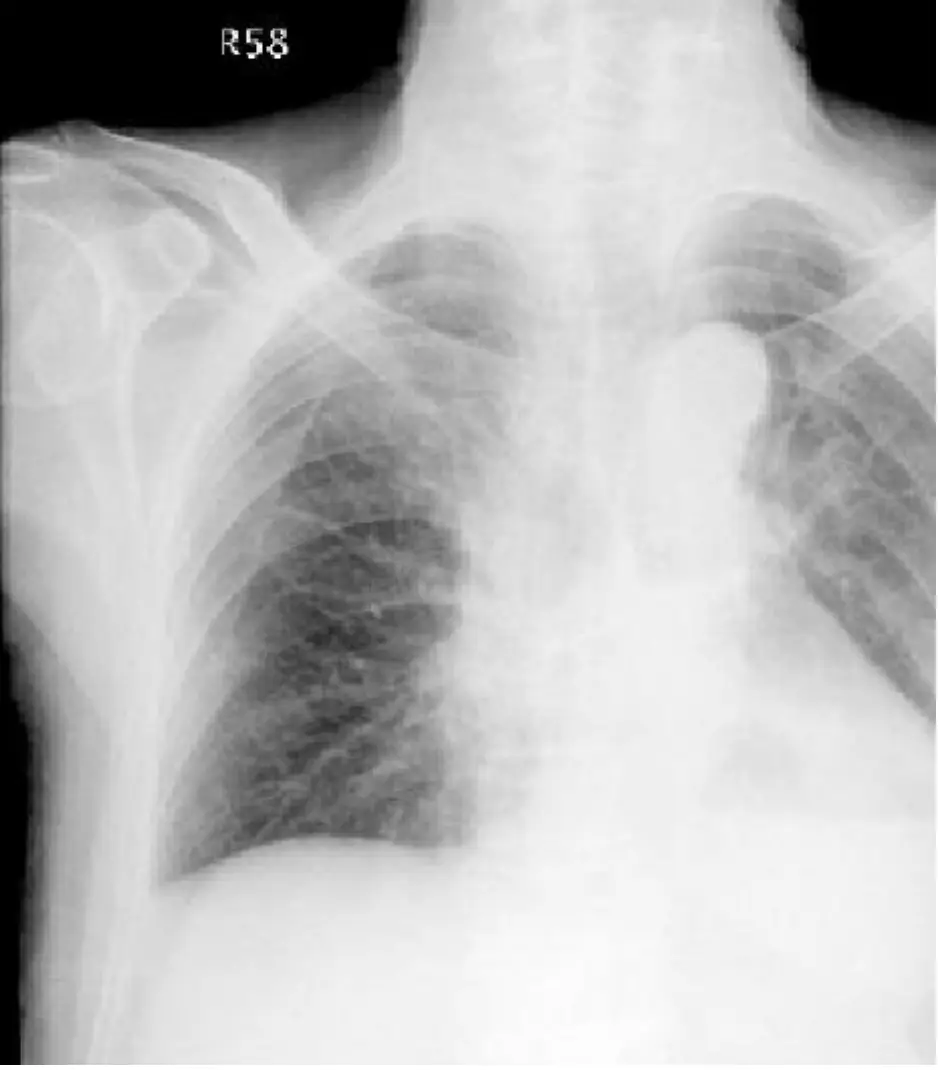

胸部X光

- 心胸比未明顯增大,無典型Kerley B線或perihilar bat-wing樣肺泡性水腫。

- 雖可見肺野稍有模糊陰影、粗濁呼吸音,卻無明顯肺充血或雙側胸腔積液,與急性左心衰的典型CXR表現不符 ([radiologyassistant.nl](https://radiologyassistant.nl/chest/chest-x-ray/heart-fai